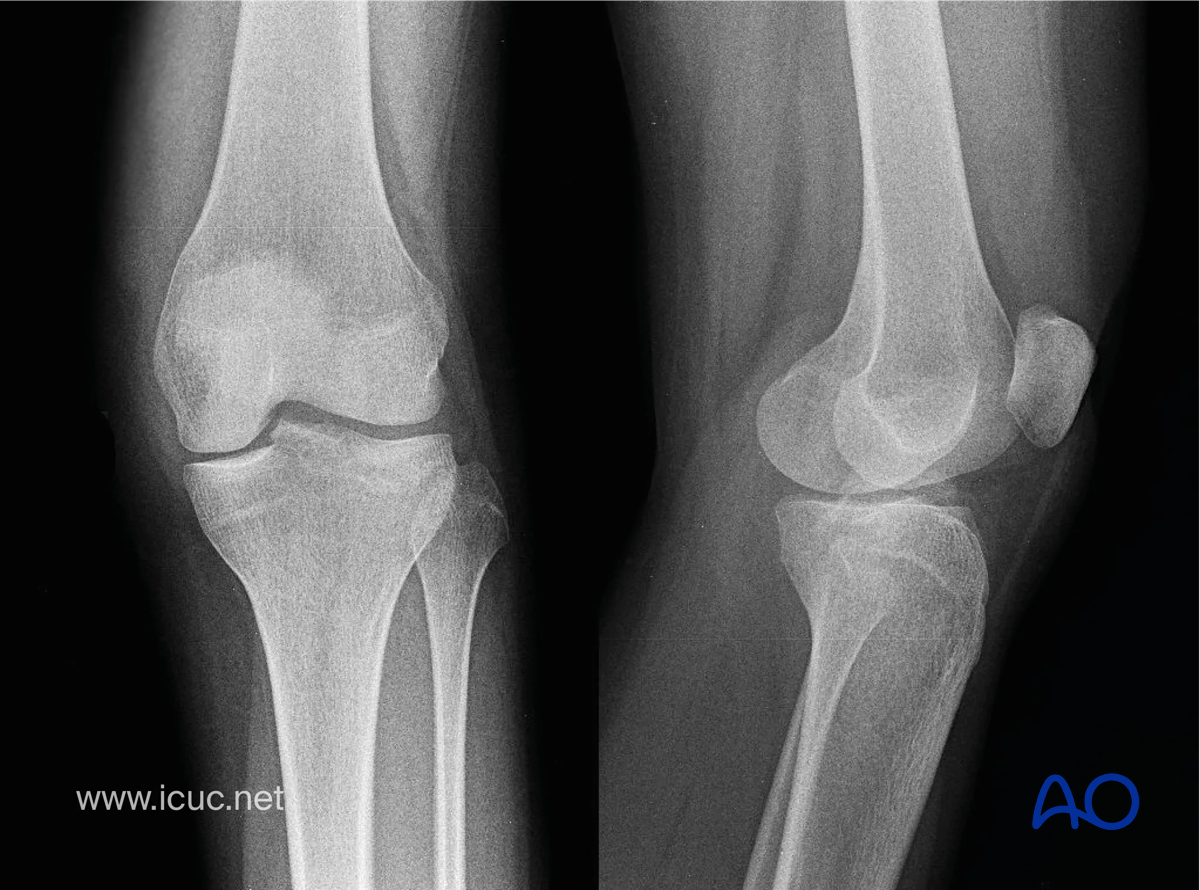

AP and lateral x-rays demonstrating avulsion of the tibial spine with slight displacement.

AP and lateral x-rays demonstrating avulsion of the tibial spine with slight displacement